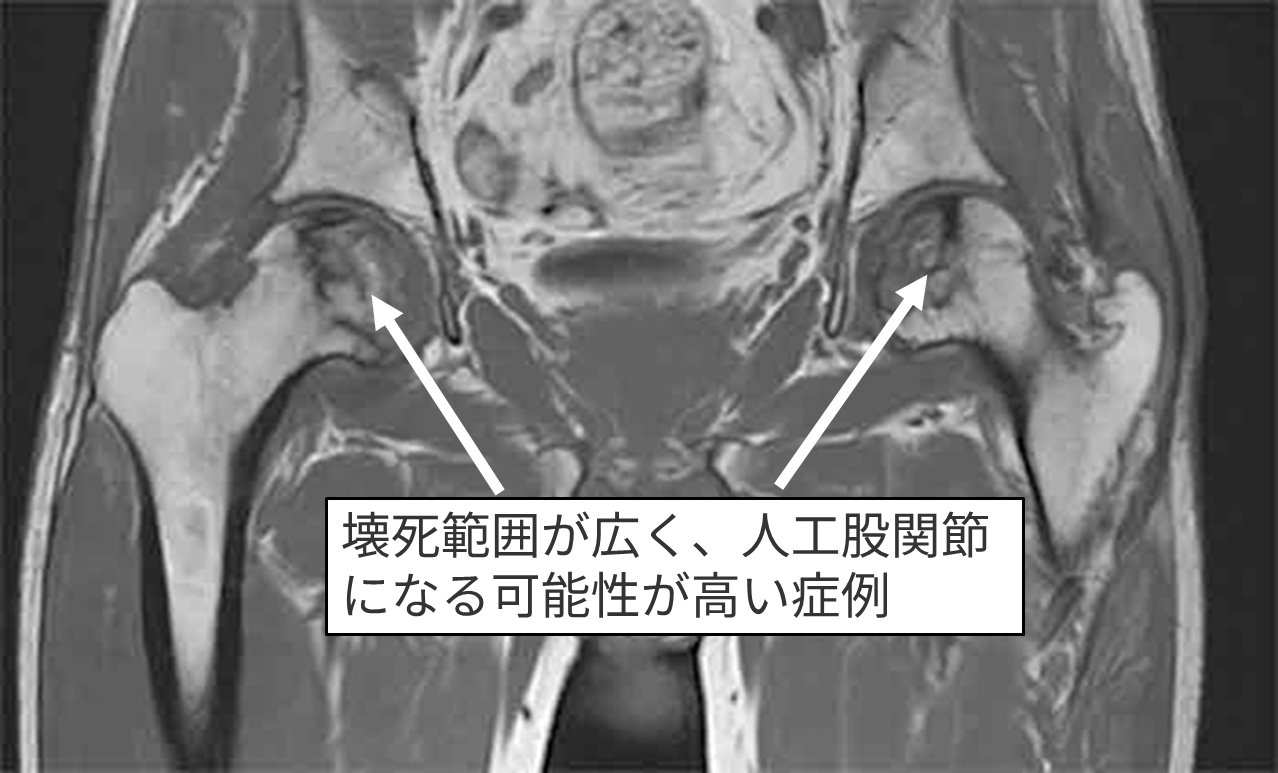

MRI検査

右Type C1 左Type C1

右Stage 2 左Stage 3A

壊死範囲が広いタイプでかかりつけ医から「いずれ人工股関節になる可能性が高い」と言われた

➡︎再生医療希望で受診 ➡︎両側の再生医療手術を施行